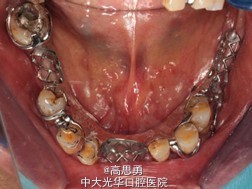

诊断: 1、牙列缺损(上颌肯氏II类I分类,下颌肯氏II类II分类) 2、#13慢性根尖周炎 3、#11、#12、#13、#21、#22、#23、#33、#42、#43、#44楔状缺损 4、慢性牙周炎 治疗计划 1、#13转牙体牙髓科做RCT 2、转牙体牙髓科对#11、#12、#13、#21、#22、#23、#33、#42、#43、#44楔状缺损 充填治疗 3、转牙周科进行牙周洁治 4、择期RPD修复 备选修复方案: 1、#13RCT后截冠后,上下颌覆盖义齿修复; 2、#13RCT后冠修复,上下颌可摘局部义齿修复; 3、#13RCT后树脂充填,上下颌可摘局部义齿修复; 4、#13拔除后,上下颌可摘局部义齿修复。 患者意愿:患者希望尽量保持#13的天然形态,要求费用尽量低,但能恢复正常咀嚼功能。 最终治疗方案:根据患者的年龄、身体状况、治疗周期、经济状况,患者最终选择方案5,即#13RCT后树脂充填,上颌结合卡环式可摘局部义齿修复;下颌可摘铸造支架式局部义齿修复。 治疗过程: 1、临床检查和#13树脂充填 对患者进行全面的口腔检查,用Z350树脂充填#13,调HE,抛光。 2、研究模型 调拌藻酸盐印模材料于2号成品托盘上取上下颌研究模,灌注石膏模型,研究分析、制定治疗计划,并制作个别托盘。 3、基牙预备 对#13近中、#23远中、#27近中、#34近中、#47近中常规制备支托凹,抛光。 4、工作模型 调拌藻酸盐印模材料于个别托盘上。做一定的边缘整塑,取上下颌研究模,灌注石膏模型。 5、试戴支架 检查支架的就位、固位可,无翘动,调HE,抛光,用蜡堤取颌位关系,上颌架,排牙,比色C4。 6、试排牙 检查义齿的就位、固位可,无翘动,观察人工牙的咬合状况,尖窝接触良好,正中颌位能重复,患者无诉不适,面容自然,外观满意。送加工厂充胶制作最终修复体。 7、试戴 检查义齿的就位、固位可,无翘动,咬合关系正确,利用咬合纸检查,上下颌尖窝接触均匀全面,抛光,患者表示满意,嘱注意事项,定期复诊。